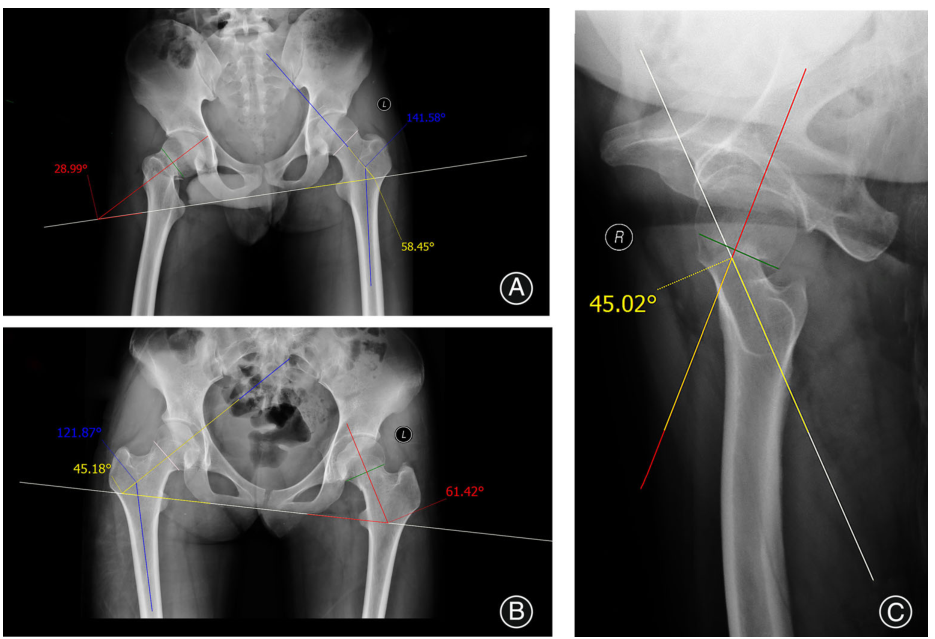

CDAC分型的测量方法 该分型可以通过测量骨盆正位片、髋关节轴位片或者CT影像中的相关角度获得。图6为偏移角的示意图,①内翻偏移型的骨盆正位偏移角度:绘制坐骨最低点的连接线(白色);在健康股骨头的头颈部交界处绘制连接线;绘制并测量颈干角,为141.58?;测量股骨颈轴线与白线的夹角,即58.45?;在骨折侧股骨头的头颈部交界处画连接线;画出绿线的垂直线与白线的夹角,即28.99?;因此,骨盆正位的偏移角度=29.46?58.45?-28.99?。②外翻偏移型的骨盆正位偏移角度:测量方法与内翻偏移型相同,骨盆入射角=16.24?61.42?-45.18?。③髋关节轴位偏移角度:在骨盆正位片上绘制股骨头轴线;在髋部轴位照片上绘制股骨头和股骨头颈部交界处的连接线;画一条绿色垂直线;髋关节偏移角度(黄色),为45.02?在这里定义股骨头向后倾斜为正值),由红线和白线的交点组成。